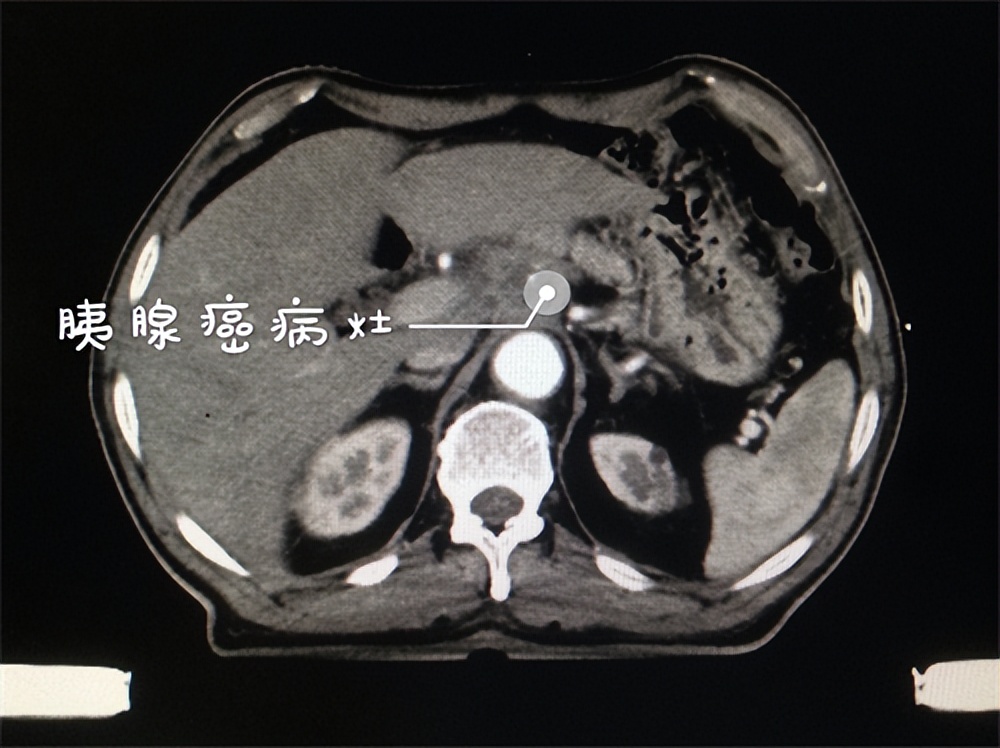

还真是那病!癌中之王——晚期胰腺癌。

胰腺癌是一种比较致命的疾病,通常很难被早期检测出来,而且治疗难度较大。胰腺位于胃后面和脾脏前面的腺体。它由头部、体部和尾部三部分组成。它的主要功能是分泌胰液和激素,从而帮助消化和调节血糖水平。胰腺癌是一种由于细胞异常增生引起的肿瘤性疾病,往往在癌症发展到晚期才被发现。

胰腺癌的症状通常很不明显,可能包括腹部疼痛、黄疸、恶心、呕吐、胃肠道问题以及消瘦。这些症状都比较常见,可能被误认为是其他疾病的表现,所以在早期被诊断胰腺癌是非常困难的。